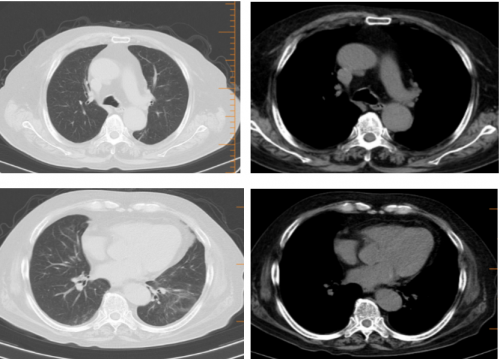

10-20胸部CT:

10-22:真菌培养:黄蓝状菌(蠕行青霉 )1cfu